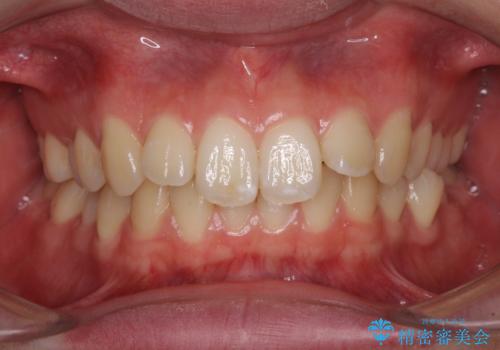

染め出しをしてエアフローで綺麗にクリーニング

担当医 歯科衛生士